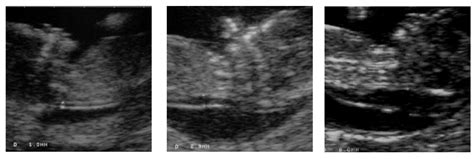

Sprando vaiskumo matavimas atliekamas ultragarsu 11-13 nėštumo savaitę (11+0 - 13+6). Tyrimo metu nustatomas vaisiaus amžius, įsitikinama, ar auga vienas vaisius, ar dvynukai, įvertinama gimdos ir placentos kraujo apytaka, gimdos kaklelio ilgis, apžiūrima, ar nematyti anomalijų (apsigimimų). Šio tyrimo metu matuojamas ir sprando vaiskumas.

Būtina įvertinti gimdą, gimdos kaklelį, kiaušides. Sprando raukšlės storis vertinamas 10-14-ąją nėštumo savaitę (norma < 3 mm).

Embriono sprando vaiskumas neturėtų būti didesnis nei 3 mm. Jeigu sprando vaiskumo matmuo yra ≥ 2,5 mm, nėščiajai rekomenduojama pirmojo ar antrojo nėštumo laikotarpio prenatalinė diagnostika (pirmenybe teikiant pirmojo nėštumo trečdalio prenatalinei diagnostikai). Kuo didesnis sprando vaiskumo matmuo, tuo didesnė chromosominių anomalijų rizika (apsigimimų).

Šio matavimo tikslumas nėra šimtaprocentinis ir priklauso nuo gydytojo patirties, vaisiaus pozicijos ir kitų veiksnių. Sprando vaiskumo matmuo ir nosies kaulo buvimas ar nebuvimas leidžia įtarti arba atmesti chromosomines vaisiaus ligas, dažniausiai 21 chromosomos trisomiją, t. y. Dauno sindromą. Jam būdinga stora vaisiaus sprando raukšlė: kuo ji storesnė, tuo Dauno sindromo tikimybė yra didesnė.

Tyrimo rezultatas bus aiškus iš karto. Svarbu, kad embriono sprando vaiskumas nebūtų didesnis nei 3 mm. Kuo didesnis sprando vaiskumo matmuo, tuo didesnė chromosominių anomalijų rizika (apsigimimų). Atminkite, kad šio matavimo tikslumas nėra šimtaprocentinis - priklauso nuo gydytojo patirties, vaisiaus pozicijos ir kt. Šio metodo patikimumas 80 proc. Ir atvirkščiai, jei sprando vaiskumo tyrimas nerodė rizikos, tai nereiškia, kad vaikutis tikrai gims sveikas.